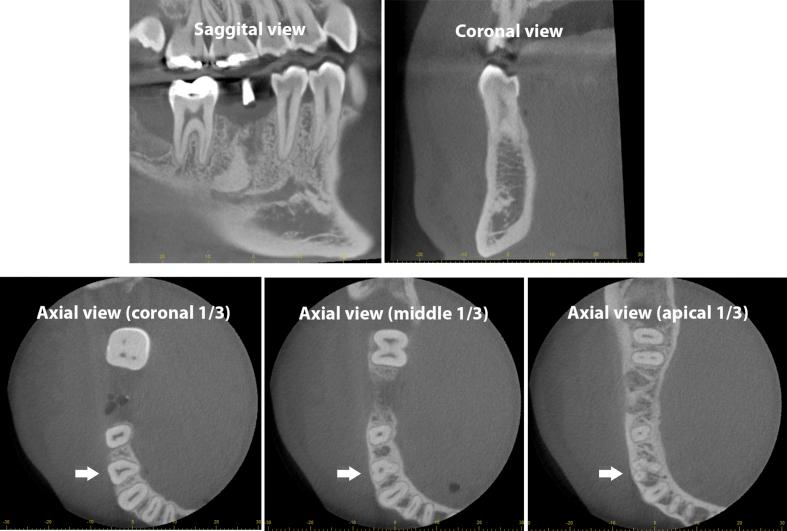

A total of 349 first mandibular premolars and 416 second premolars from CBCT images with 0.125-mm voxel size and 60 × 60 mm field of view were evaluated. Number of roots, root canals, and C-shaped canals were recorded and statistically analyzed using chi-square test. Root canal configurations were defined according to the Vertucci's classification. Levels and distances of separated multiple canals were reported.

Multiple roots in mandibular first premolars were found at 5.73% while none of second premolars had. Multiple root canals were found in the first premolars at 19.48% and the second premolars at 3.85%. C-shaped canals (C1/C2) were found in the first premolars at 3.72% and the second premolars at 0.48%. All parameters in the first premolars were significantly higher than in the second premolars (p < 0.01). The majority of multiple root canals were defined as Vertucci's type V (1-2 canals). Multiple root canals were frequently separated at the middle level of roots about 6.5-7.0 mm from the cementoenamel junction.

下颌第一前磨牙多根发生率为5.73%,下颌第二前磨牙未见多根情况。下颌第一前磨牙多根管发生率为19.48%,下颌第二前磨牙为3.85%。下颌第一前磨牙C形根管(C1/C2)发生率为3.72%,下颌第二前磨牙为0.48%。下颌第一前磨牙的所有参数均显著高于下颌第二前磨牙(p<0.01)。大多数多根管被定义为Vertucci V型(1-2个根管)。多根管常于牙根中部距牙骨质釉质界约6.5-7.0mm处分离。